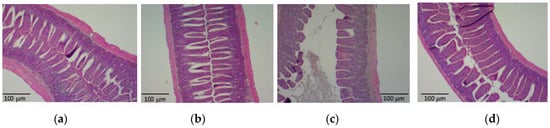

3.2. PHGG Protected the Gut Environment